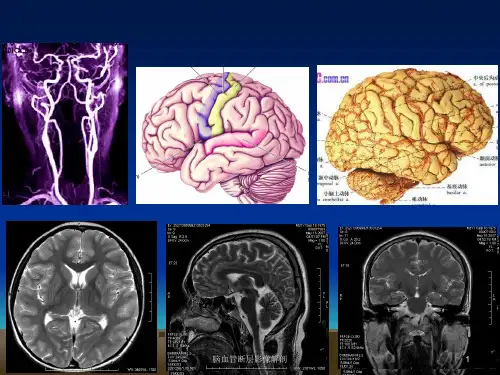

脑池断层影像解剖